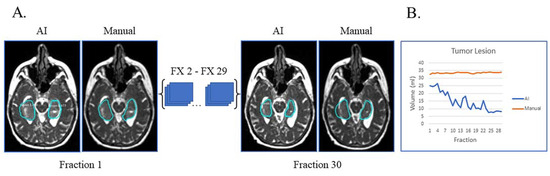

Lastly, unusual findings outside the training of a dataset can cause AI failures, as shown in Figure 4. This patient had sub-total resection of disease with resection cavity and tumor lesion. After surgery, the left occipital ventricular horn became trapped by the central tumor with large expansion of the ventricle and surrounding edema (Figure 4A). This case highlights that anatomic changes seen during RT can be unique/unexpected, which can affect the network’s ability to segment. Despite these challenges, the network was still able to segment resection cavity with relatively high accuracy (Figure 4B).

Figure 4.

Case of network failure due to unusual anatomy. Patient had sub-total resection with resection cavity and tumor lesion with no progression of disease during and immediately after treatment. (A) Auto-segmentation (left) and manual (right) contours of tumor lesion (cyan) and resection cavity (red) at the first and last treatment fractions (FX) shown on MRI-linac bSSFP. The large resection cavity communicated with ventricle, which led to the network’s failure to detect an obvious tumor lesion surrounding resection cavity at all timepoints. (B) Still, AI-derived volumes (blue) compared to manually segmented volumes (orange) for resection cavity across treatment.